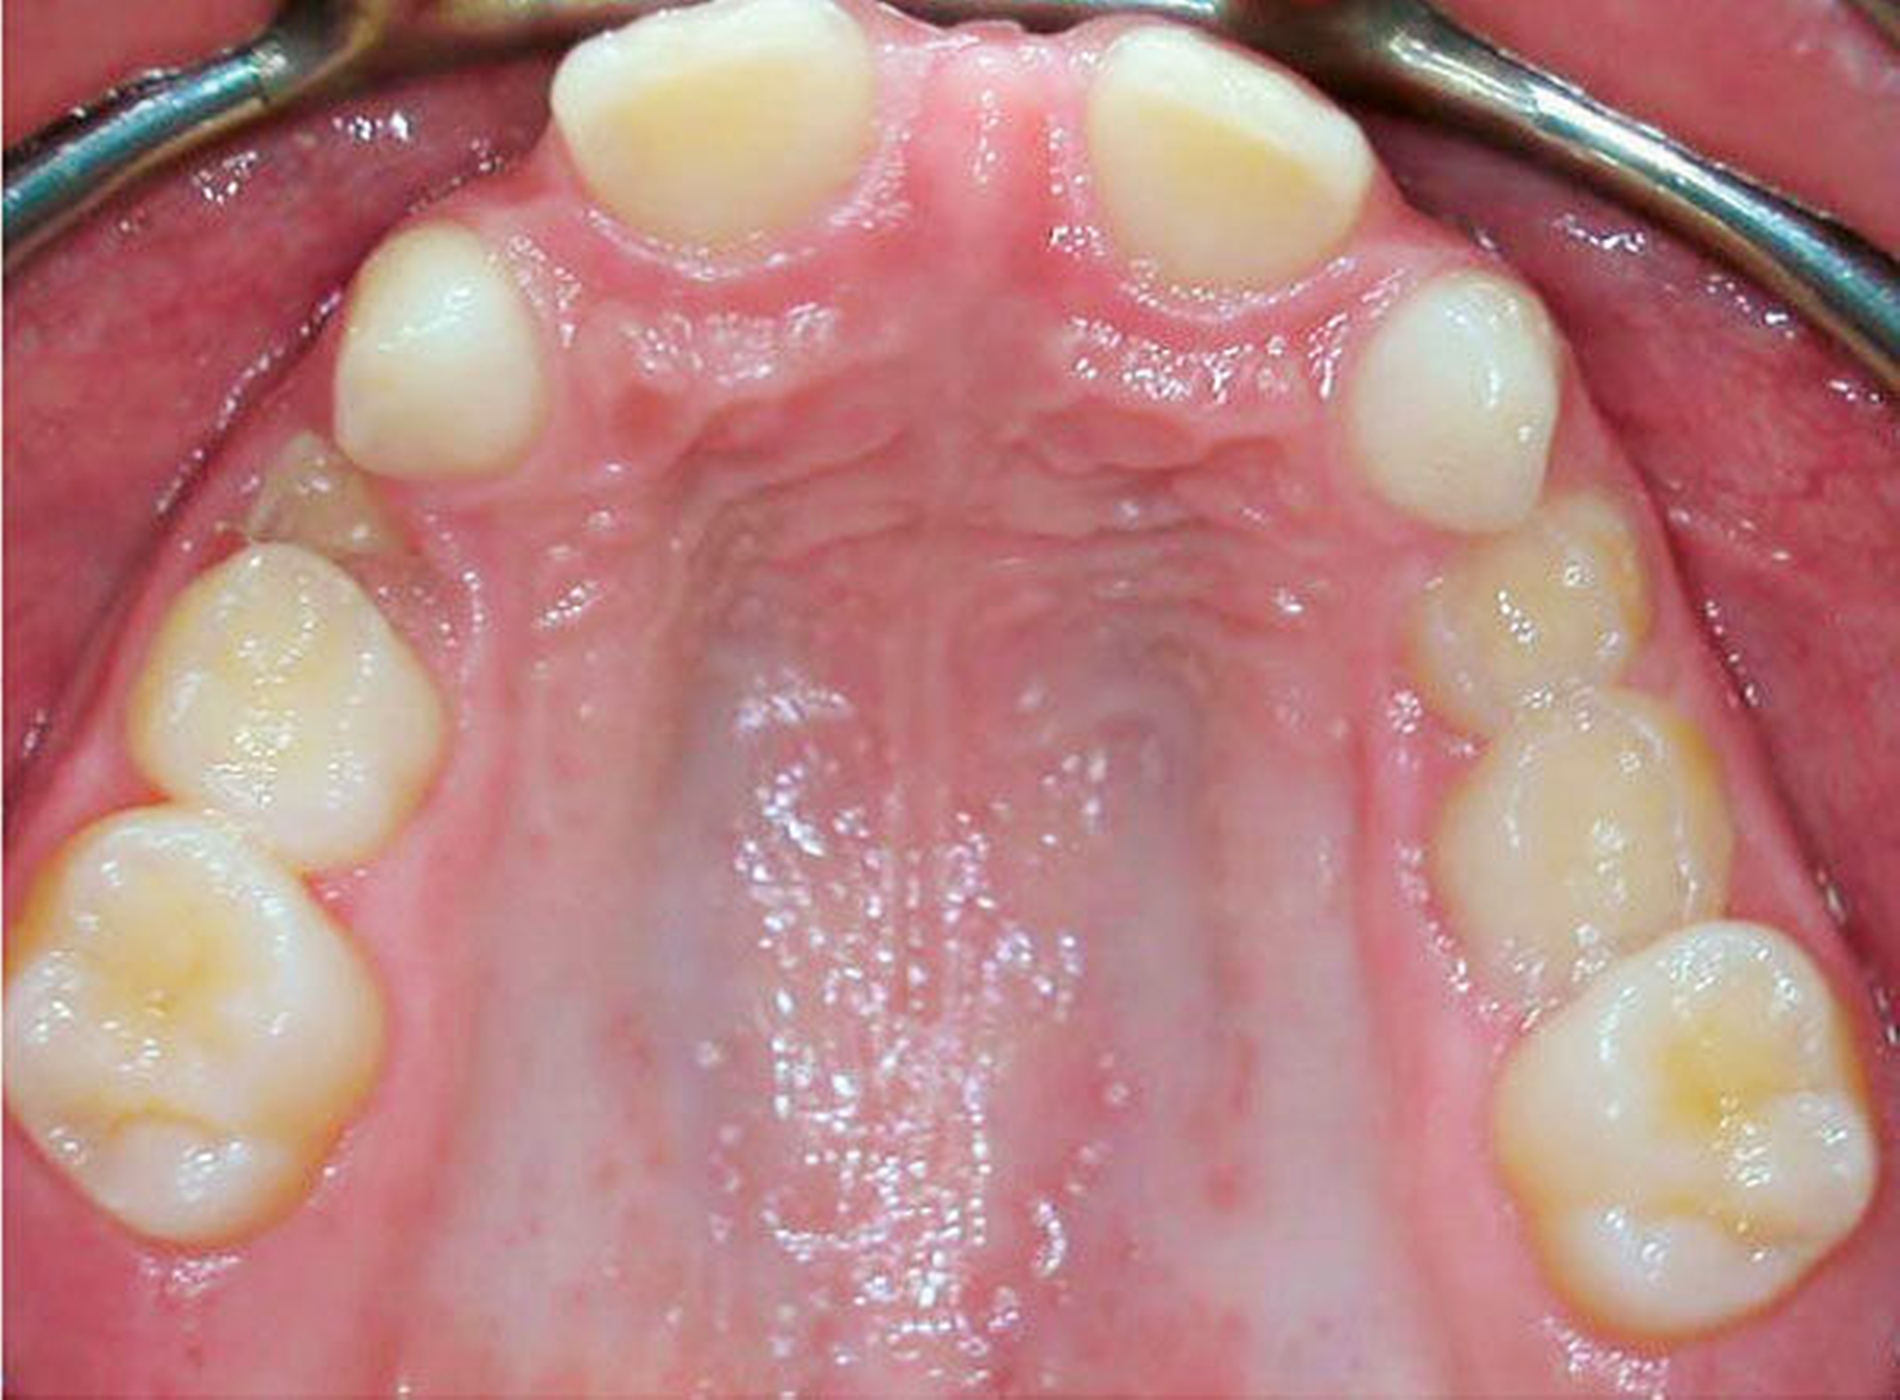

Die zehnjährige Patientin wurde uns von der Kieferorthopädin zur Wertung möglicher chirurgischer Maßnahmen bei insgesamt acht Nichtanlagen (Abbildung 1a bis c) vorgestellt. Im OPG stellt sich das Fehlen von drei permanenten Zähnen im I. Quadranten, von vier im II. Quadranten und einem im III. Quadranten dar (Abbildung 1c). Aufgrund des noch jungen Alters der Patientin zum Zeitpunkt der Erstvorstellung und des damit noch verbundenen Vorhandenseins der Milcheckzähne 73 und 83 entschieden wir uns für das folgende kieferorthopädisch-kieferchirurgische Vorgehen (Abbildung 2):

3. Autogene Transplantation der unteren Milcheckzähne 73 und 83 in die vorher geschaffenen Lücken in Position 12 und 22 (Abbildungen 3a, b) sowie

4. Ausgleichstransplantation des Zahns 35 in Position 24 mit dem Ziel einer gleichmäßigen Verteilung von jeweils einem Prämolaren pro Quadranten (Abbildung 3b).